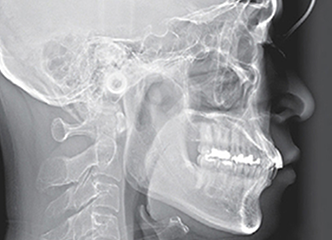

セファロ

安全で精度の高い治療をご提供するため、歯科用CTや口腔内スキャナーの導入など医療設備を充実させています。また、安心・安全な治療をご提供するため、器具の滅菌や診療空間の空気清浄化に努めています。